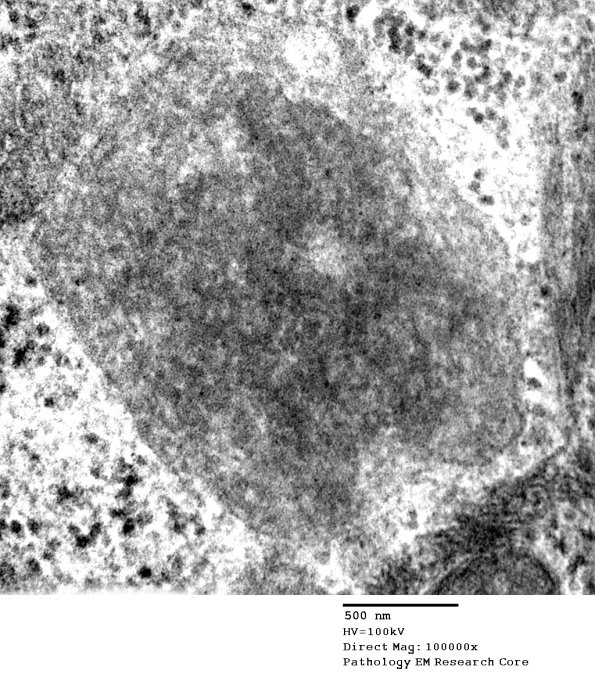

One more inclusion. There were no fingerprint bodies or granular osmiophilic cytosomes found in the case. (electron micrograph) ----

Addendum Comment: The findings of curvilinear inclusions in sweat ducts/glands are compatible with the diagnosis of neuronal ceroid lipofuscinosis